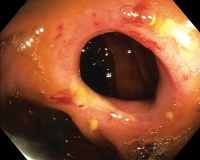

Endoscopic therapy for stricture before

Close endoscopic view inside a hollow organ.

Endoscopic therapy for stricture after